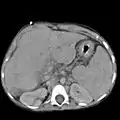

The hepatorenal recess[1] (subhepatic recess, pouch of Morison or Morison's pouch) is the subhepatic space that separates the liver from the right kidney. As a potential space, the recess is not normally filled with fluid. However, fluid can collect here in circumstances where the abdomen fills with fluid, such as hemoperitoneum. This fluid may be seen on ultrasound or computed tomography (CT scan).

Since it is a potential space, the hepatorenal recess is not normally filled with fluid. However, this space becomes significant in conditions in which fluid collects within the abdomen (most commonly ascites and hemoperitoneum). The intraperitoneal fluid, be it blood, ascites, or dialysate, collects in this space and may be visualized, most commonly via ultrasound or computed tomography (CT) scanning. As little as 30 or 40 ml of fluid in the abdominal cavity may be visualized in this space.